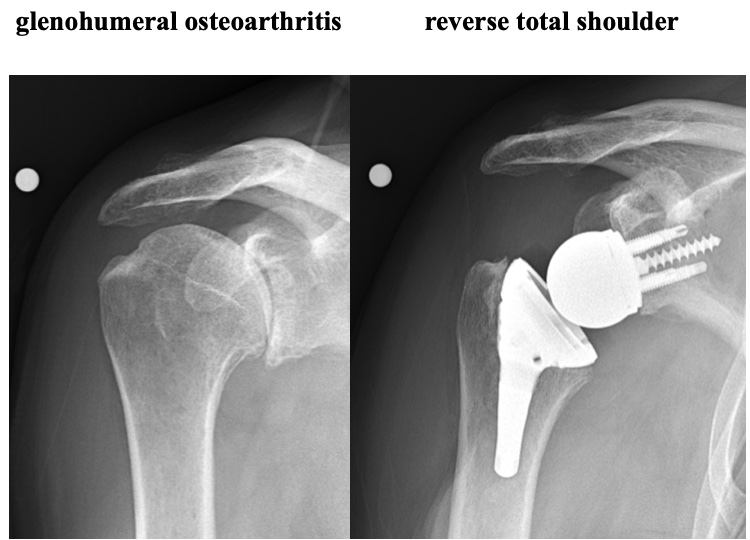

Arthritis is a common condition that can affect all joints in the human body. Arthritis results in the loss of the smooth cartilage surface that covers the ends of a bone in a joint. In addition, arthritis can result in deformity of the joint surfaces. When this occurs in the shoulder (glenohumeral joint) patients experience pain, loss of motion, and functional limitations. The most common form is osteoarthritis.

Osteoarthritis results in the gradual destruction of the articular cartilage of the humeral head and glenoid. This is usually a gradual process that occurs over the course of many years. In addition, the normal shape of the spherical (round) humeral head and matching glenoid socket are lost. The earliest sign of glenohumeral osteoarthritis is shoulder pain and mild loss of shoulder motion. In many cases, early osteoarthritis is confused with shoulder impingement syndrome and rotator cuff disorders. In most cases the diagnosis is easily determined with appropriate x-rays of the shoulder.

Shoulder replacement is indicated when there is advanced glenohumeral osteoarthritis. Most patients undergo replacement surgery because of shoulder pain. Shoulder replacement is similar in concept to hip replacement. The humeral head is replaced with a metallic implant. Anatomic total shoulder replacement includes replacement of the glenoid socket as well as the humeral head with implants that mimic the normal anatomy.

Anatomic total shoulder replacement requires a good rotator cuff. The replacement glenoid is made of plastic (ultra high molecular weight polyethylene). While most severely arthritic shoulders require glenoid replacement, there are occasional cases that can be treated with a humeral head resurfacing or a humeral head replacement can be performed. The ream and run procedure with a humeral head replacement and smoothing of the glenoid is an option for physically active, often younger patients, who want to participate in heavy physical activities and avoid the potential problems associated with anatomic glenoid replacement. The are some patients with osteoarthritis who have severe glenoid bone deformities and/or rotator cuff tearing who are treated with a reverse total shoulder. Reverse total shoulder was developed for the treatment of shoulder with severe rotator cuff tears. More recently, use of reverse total shoulder has expanded to some osteoarthritic shoulders. This is currently considered an off-label use of reverse total shoulder.